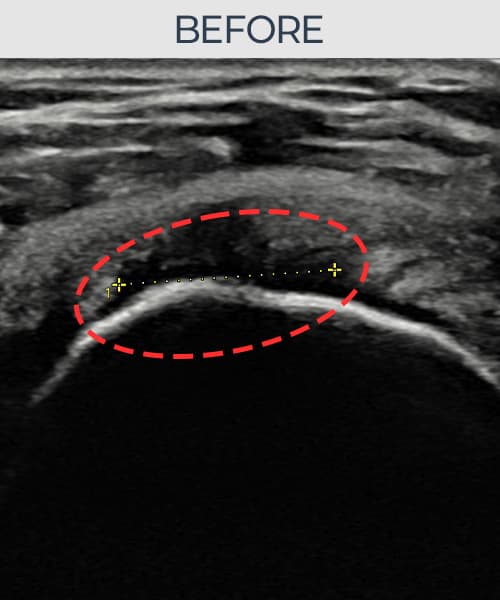

실제 환자의 시술 전후 초음파 영상입니다.

수술 없이 이뤄낸 회복을 직접 확인하세요.

모든 초음파 영상은 실제 환자의 동의를 받아 게시하였습니다. 개인차가 있으며 동일한 결과를 보장하지 않습니다.

[촬영시기:22.09.06]

[석회분쇄흡입술] 좌측 어깨 통증으로 팔을 옆으로 올리기 어려워진 60대 남성 환자로, X-ray에서 좌측 극상근건 내 석회 침착이 확인되어 석회분쇄흡입술을 시행하였습니다.